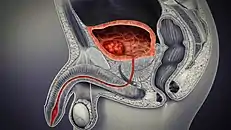

Bladder location and associated structures in the male

In males, the prostate gland lies outside the opening for the urethra. The middle lobe of the prostate causes an elevation in the mucous membrane behind the internal urethral orifice called the uvula of urinary bladder. The uvula can enlarge when the prostate becomes enlarged.

The bladder is located below the peritoneal cavity near the pelvic floor and behind the pubic symphysis. In males, it lies in front of the rectum, separated by the recto-vesical pouch, and is supported by fibres of the levator ani and of the prostate gland. In females, it lies in front of the uterus, separated by the vesico-uterine pouch, and is supported by the elevator ani and the upper part of the vagina.[8]